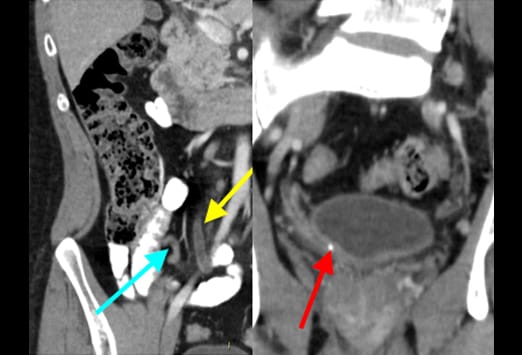

Dieser 81-jährige Mann wurde mit Schmerzen im rechten Unterbauch vorstellig. Die CT- Untersuchung zeigt eine ausgeprägte Divertikulose des Kolons mit einer Sigmadivertikulitis. Es zeigen sich eine mesenteriale Infiltration (gelber Pfeil) sowie eine adhärente normal erscheinende Appendix (blauer Pfeil). Auch wenn eine Appendizitis die häufigste Diagnose bei älteren Patienten ist, sollten andere Diagnosen wie eine rechtsseitige Divertikulitis oder eine Sigmadivertikulitis bei elongiertem Sigma, eine entzündliche oder infektiöse Kolitis, ein perforiertes Kolonkarzinom oder eine mesenteriale Ischämie mit in Betracht gezogen werden.